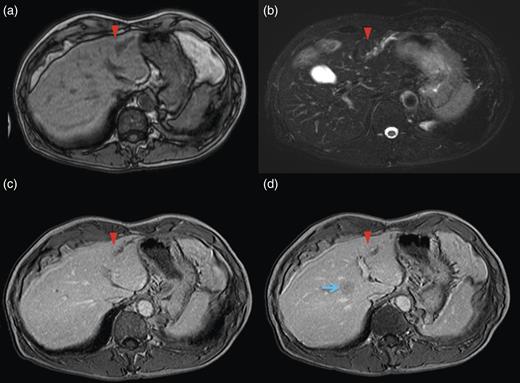

Computed tomography (CT) demonstrated two solitary lesions in segment (S) eight. Furthermore, S3 hepatic duct dilatation was clearly detected on CT scanning (Fig. 1).

Magnetic resonance imaging (MRI) of the lateral segment lesion showed an irregular line shape lesion: hyper-intensity in T2-weighted; hypo-isointense in T1-weighted image (Fig. 2). These CT and MRI findings supported the identification of a fulfilment of tumour in B3. Endoscopic retrograde cholangiopancretography (ERCP) demonstrated a stricture involving the B2 and B3 hepatic ducts but not involving the left hepatic duct. Considering the patient's medical history along with the clinical features, the final diagnosis was secondary liver metastases due to primary descending colon adenocarcinoma, with the possibility of peripheral cholangiocarcinoma.